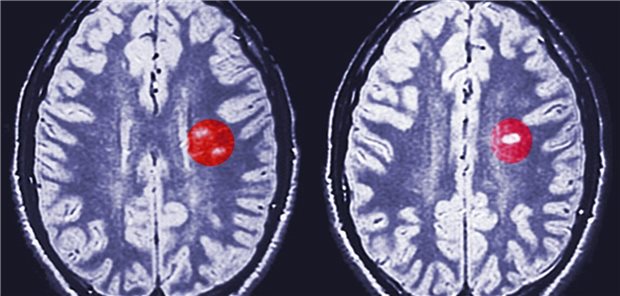

7-Jahres-Daten belegen günstiges Nutzen-Risiko-Profil von Ofatumumab